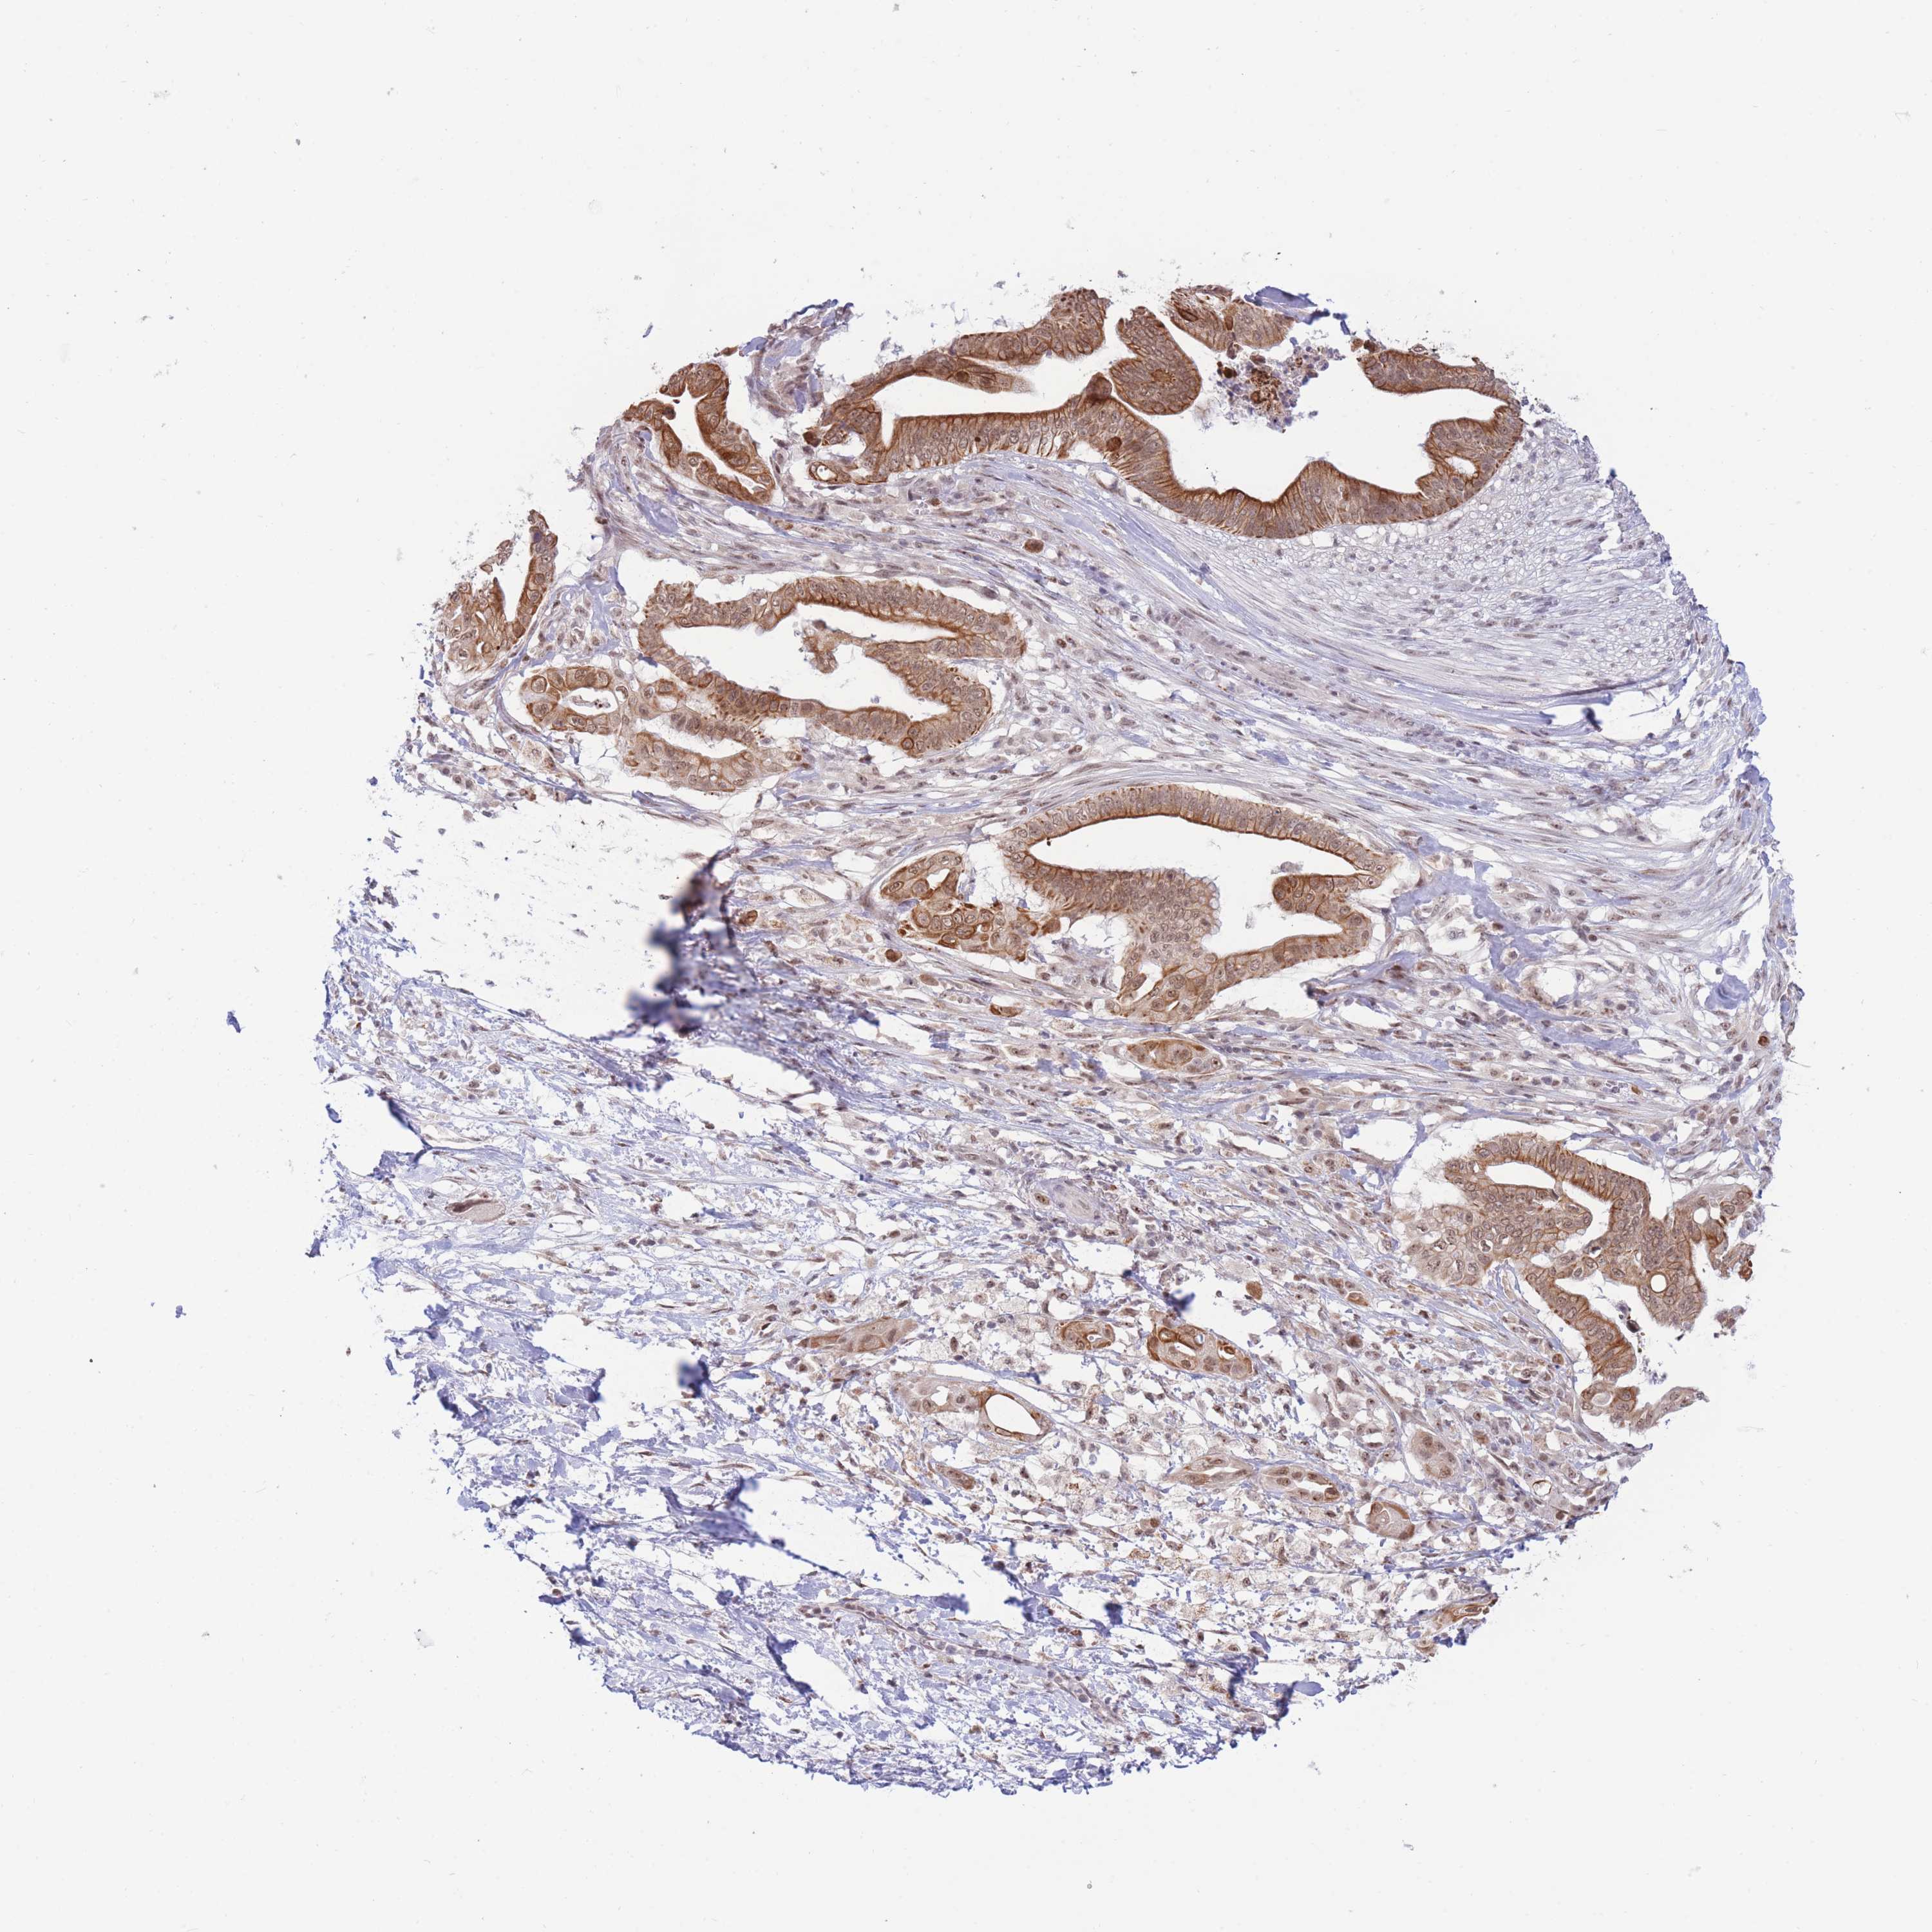

PANCREATIC CANCER - Protein expressioni

A mouse-over function shows sample information and annotation data. Click on an image to view it in a full screen mode. Samples can be filtered based on level of antibody staining by selecting one or several of the following categories: high, medium, low and not detected. The assay and annotation is described here.

Note that samples used for immunohistochemistry by the Human Protein Atlas do not correspond to samples in the TCGA dataset.

Antibody stainingi

Antibody staining in the annotated cell types in the current human tissue is reported as not detected, low, medium, or high, based on conventional immunohistochemistry profiling in selected tissues. This score is based on the combination of the staining intensity and fraction of stained cells.

Each image is clickable and will lead to virtual microscopy that enables deeper exploration of all samples and also displays staining intensity scores, fraction scores and subcellular localization as well as patient and tissue information for each sample.

Antibody HPA051181

Antibody HPA061454

Antibody CAB069406

Staining

High

Medium

Low

Not detected

Intensity

Strong

Moderate

Weak

Negative

Quantity

>75%

75%-25%

<25%

None

Location

Nuclear

Cytoplasmic/membranous

Cytoplasmic/membranous,nuclear

Adenocarcinoma, NOS